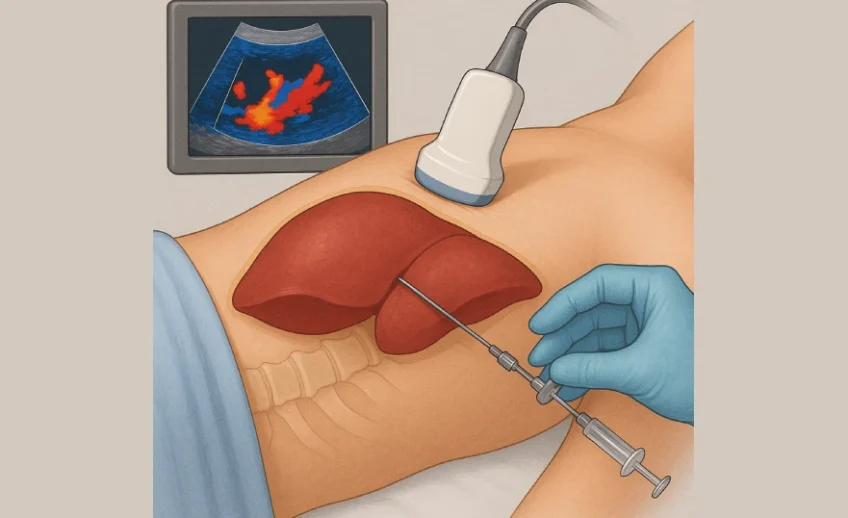

A liver biopsy is a medical procedure that removes a small sample of liver tissue for laboratory examination to diagnose, stage (e.g., fibrosis/cirrhosis), and monitor liver diseases. Common methods include percutaneous…